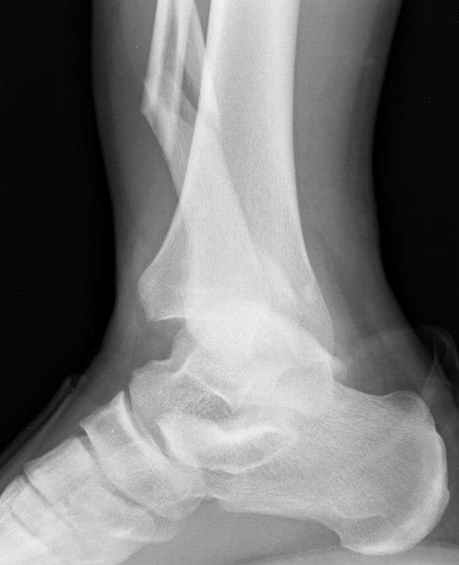

Конечно, компьютерный томограф более информативный метод, но с помощью недорогого обычного стандартного в нейтральном положении стопы: прямого, бокового и косой (ankle mortise) ренгенологического метода можно получить полную информацию о повреждении голеностопного сустава, а сравнительный снимок с другой стороны подтвердить наличие повреждения.

При реконструкции голеностопа, о важности восстановления длины малоберцовой для профилактики пост травматического артроза разбирали в предыдущих дискуссиях. Нарушенную биомеханику голеностопа без восстановления длины малоберцовой, не восстановить только швом медиальной связки.

Расширенная медиальная щель более чем на 4 мм и укорочение малоберцовой более чем 2 мм, а перелом заднего края большеберцовой смещения более 2мм с вовлечением 30% поверхности сустава, считается отходом от нормы голеностопного сустава, и подлежит к оперативному вмещательству.

Здесь похожий случай трехнедельной давности, перелом почти сросся и была укорочена малоберцовая, на операции длину малоберцовой смогли восстановить только после того, когда проксимальнее пластины ввели шуруп и использовали его как толкатель, с помощбю дистракционого инструмента (lamina spreader).

Меньше всего волнует положение медиальной лодыжки - в любое время можно провести остео или реостеосинтез, при несращении можно просто резецировать без ущерба для движений в голеностопе. Здесь обошлись фиксацией одним 4 мм канюлированным шурупом.